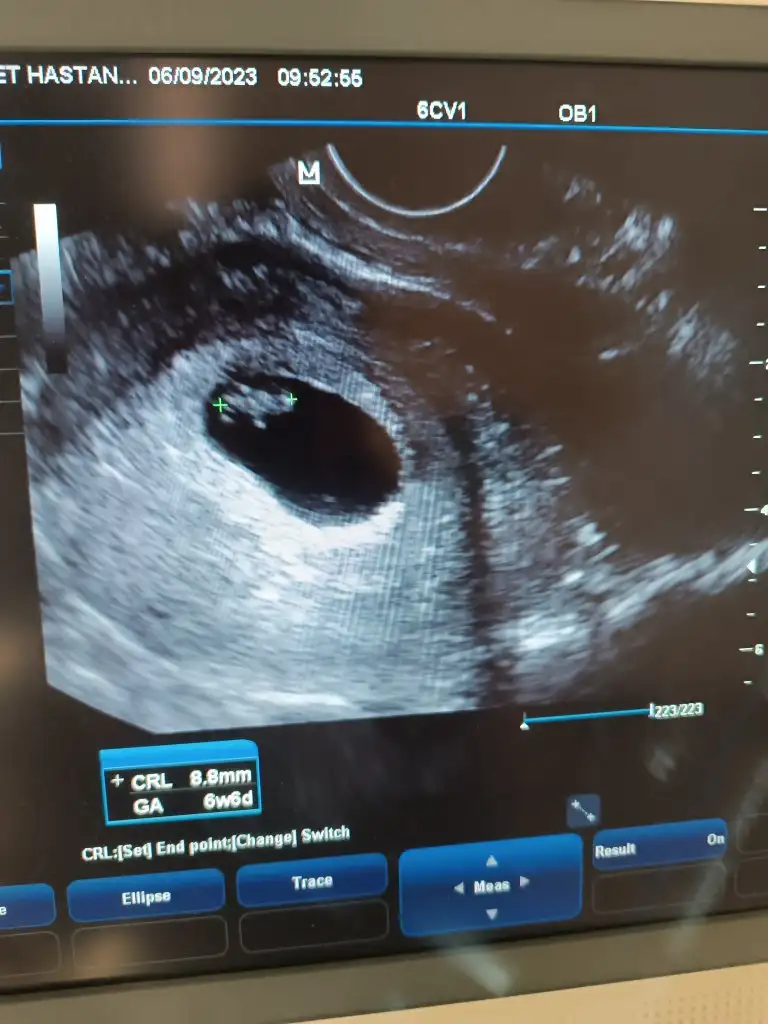

@AnlatilmazYasanir canım benimkine de bakar mısın.üçüncü gebeliğim.6 haftalık karından ultrason.ilk resimde sağda duruyor bebek,sonraki resimlerde solda anlayamadım bende.doktor açısını değiştirmiş herhalde

Bizede tahmin yapar mısınız 6+6 gunlukken çekildi VAJİNAL USG